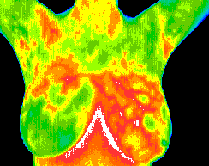

Then, there is breast thermography. Breast thermography measures heat emissions from breast tissue (cancer creates heat) and identifies changes in breast tissue. Dr. Grout: “At least five important studies published between 1980 and 2003 document that breast thermal imaging is a major advancement in identifying breast cancers not only with greater sensitivity and specificity, but also years earlier than with any other scientifically tested medical technology.”